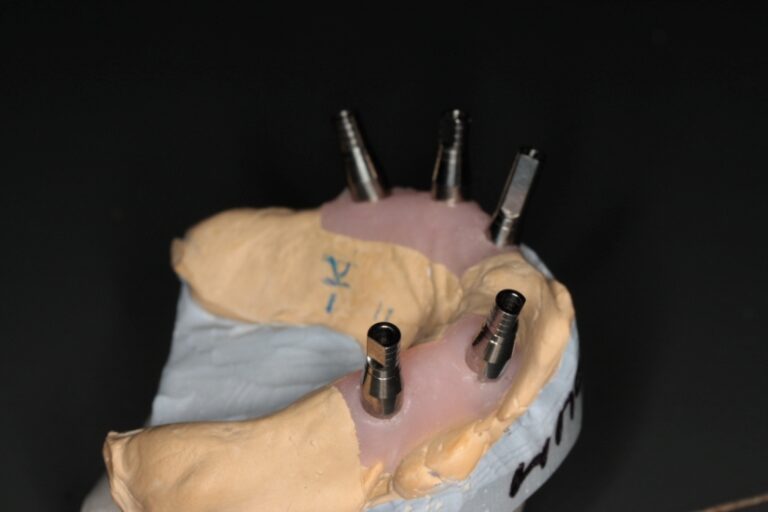

Photo 5a, b. Finished structure is fixed with the screws.